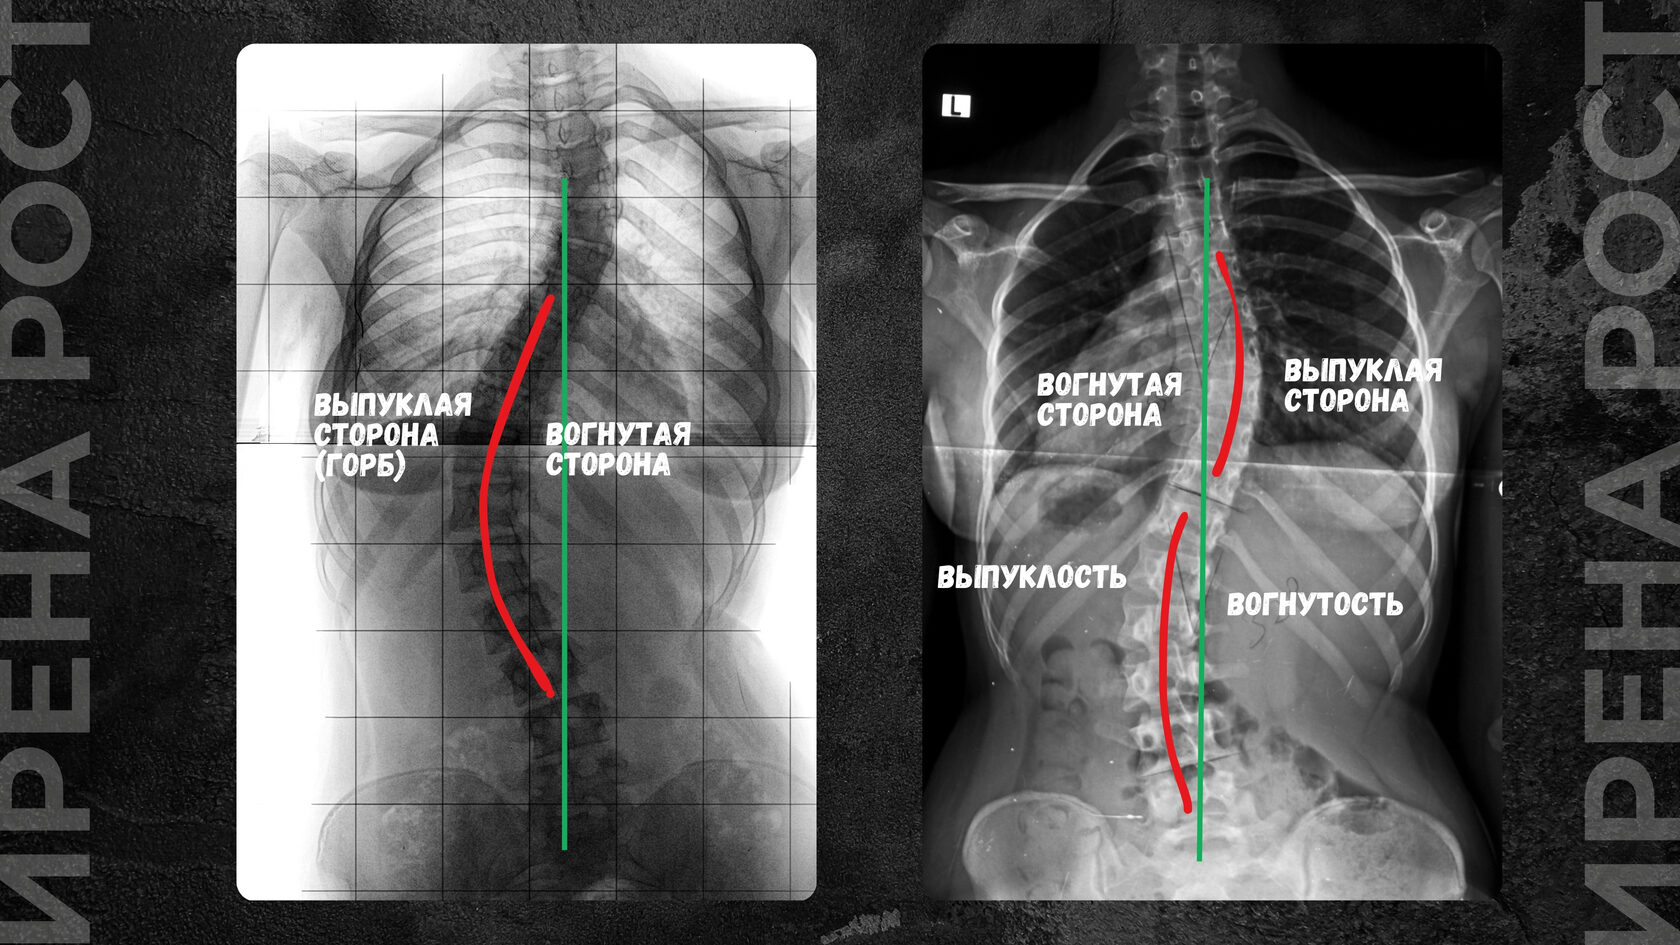

Реберный горб формируется при искривлении позвоночника в шейно-грудном, грудном или грудо-поясничном отделах, начиная со II степени искривления. Он появляется при вовлечении грудной клетки в сколиотическую дугу и ротацию (поворот) позвоночника. Сколиотическая дуга по мере ее увеличения, увеличения градусов отклонения позвоночника от вертикальной нормы, вовлекает в процесс и ребра, которые крепятся к позвонкам.

Так, со стороны сколиотической дуги ребра начинают сжиматься, создавая выпуклость полости грудной клетки, создавая реберное выпячивание (горб), а со стороны, противоположной дуге, ребра, наоборот, растягиваются, создавая сплющенность (впуклость) грудной клетки.